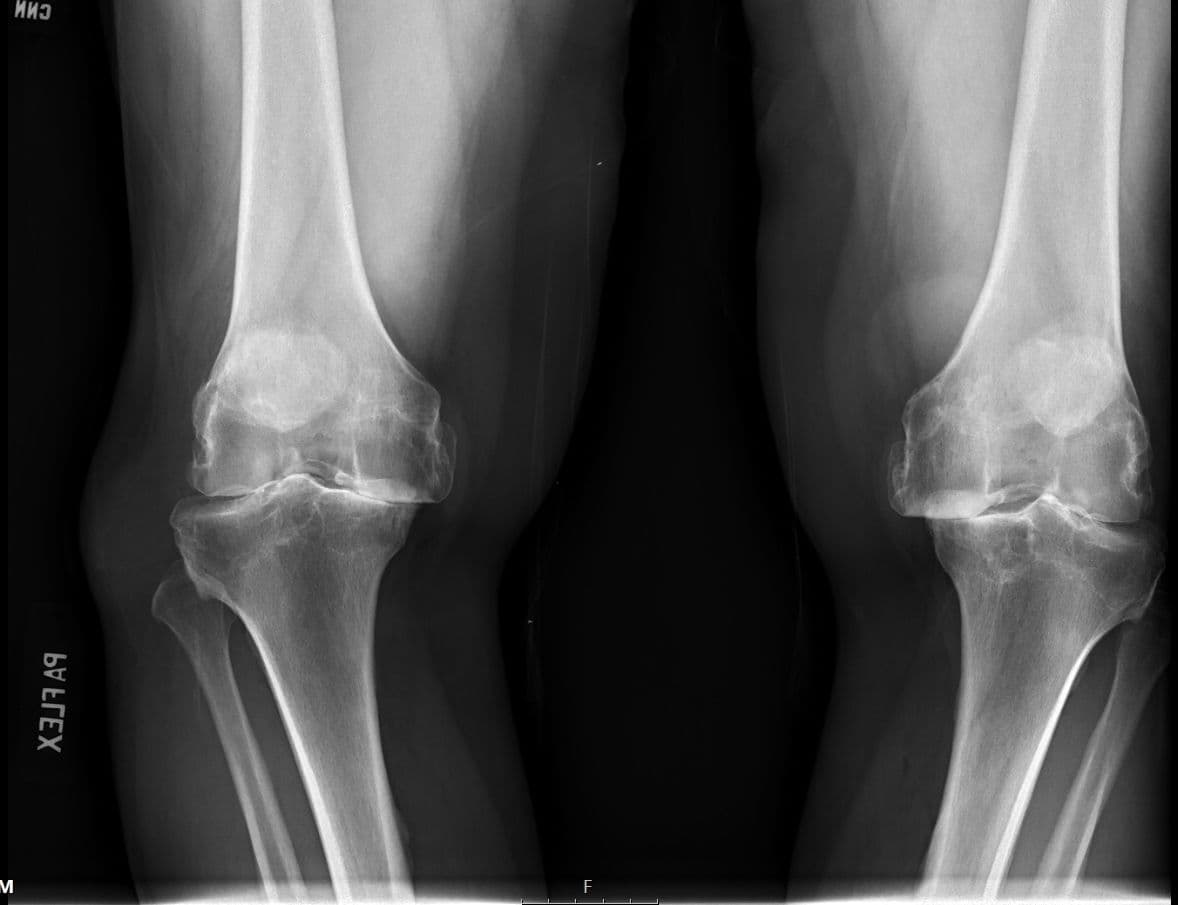

Total Knee Arthroplasty (Cementless, Robotic-assisted)

D. Gordon Allan, James Lieber